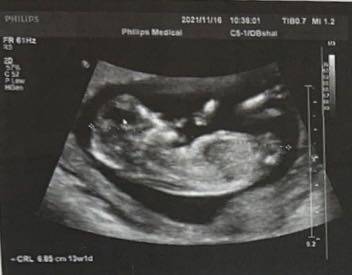

有没有宝妈会看nt图呀~想知道是男孩女孩

journal_insert_pic_1674664694

其实通过这些是看不出来的,而且也不准确,在怀孕期间不要想太多,我觉得只要宝宝发育好的话就可以。

你好。我们是判断不了男宝宝跟女宝宝的,孕期定期检查,我觉得宝宝健康就好的。祝心想事成 。

你好,对于宝宝是男孩女孩,怀孕的单子、数据、表现是判断不出来的,等到生下来才是最靠谱的。

你好亲爱的,通过这个来判断男孩女孩是不太准确的哈。那么这个男孩女孩都是我们最爱的宝贝哈,我们要给他同等的关爱和呵护,也祝你可以如愿以偿,心想事成,祝你好运加油????